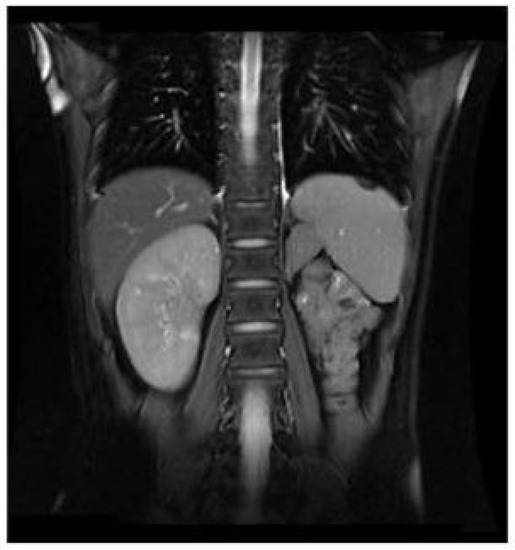

Figure 6.

MRI demonstrated the atrophy of left kidney.

Selected MRI images of the pelvis. (A) Pelvic MRI demonstrated a highly dilated vagina with internal fluid measuring 10.2 × 7.3 × 13.2 cm (yellow arrow). (B) Left ureter was dilated (yellow arrow), and the ectopic orifice of the left ureter was located at the vagina.